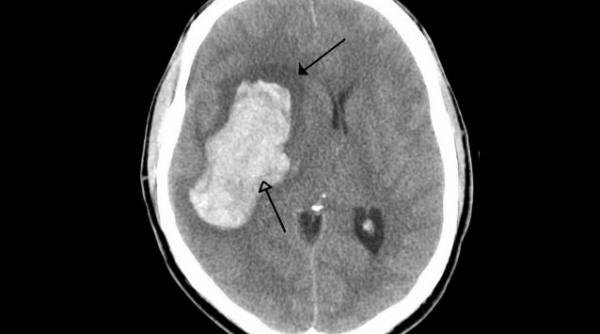

60.000 de români suferă anual un accident vascular cerebral. Bolile cerebrovasculare, una dintre principalele cauze de deces în România

Avertismentul neurologilor: TINERII, din ce în ce mai afectaţi de BOLILE BĂTRÂNETII. Care sunt cauzele